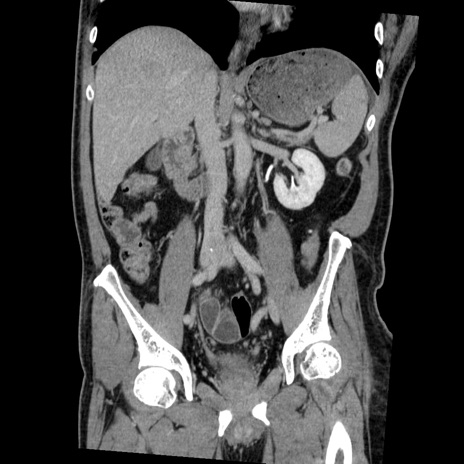

症例22(冠状断像)

【症例】50歳代男性

【主訴】腹痛

【現病歴】AVMからの被殻出血のため回復期リハ病棟入院中。 本日午後3時頃急に下腹部痛が出現した。

【既往歴】AVM、被殻出血、虫垂炎、高血圧

【身体所見】意識晴明、左半身不全麻痺、会話の理解は良好、36.5°C、腹部:膨隆、全体に板状硬、下腹部正中に圧痛点あり、反跳痛-、筋性防御不明、右下腹部にope scar

【データ】WBC 9400、CRP 0.06

横断像